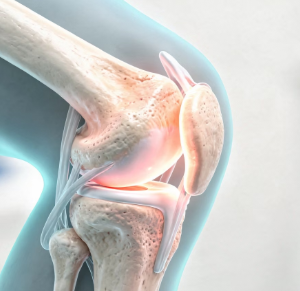

무릎에 물이 찬다는 것은 관절 안에 관절액이 과도하게 증가한 상태를 말합니다.

관절액은 무릎 관절을 보호하고 움직임을 부드럽게 해주는 역할을 합니다.

하지만 염증이나 손상이 생기면 관절을 보호하기 위해 액체가 과다 분비되면서 붓게 됩니다.

즉, 무릎에 물이 차는 것은 관절 내부에 문제가 생겼다는 신호일 수 있습니다.